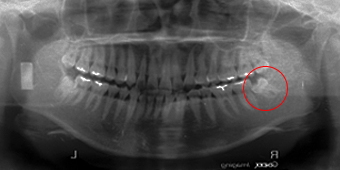

右側の下顎水平埋伏智歯は上部に埋伏している為簡単ですが、左側は水平より下向きに埋伏し位置も深い為右側よりは少し難しく10分程度です。